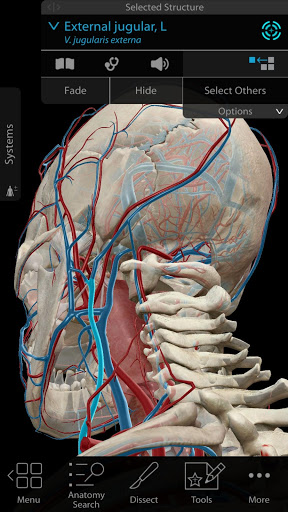

Additional nerves, arteries, and veins in the head and neck region.

Tag structures! Use the new 3D labels feature to show the name of multiple structures on screen.